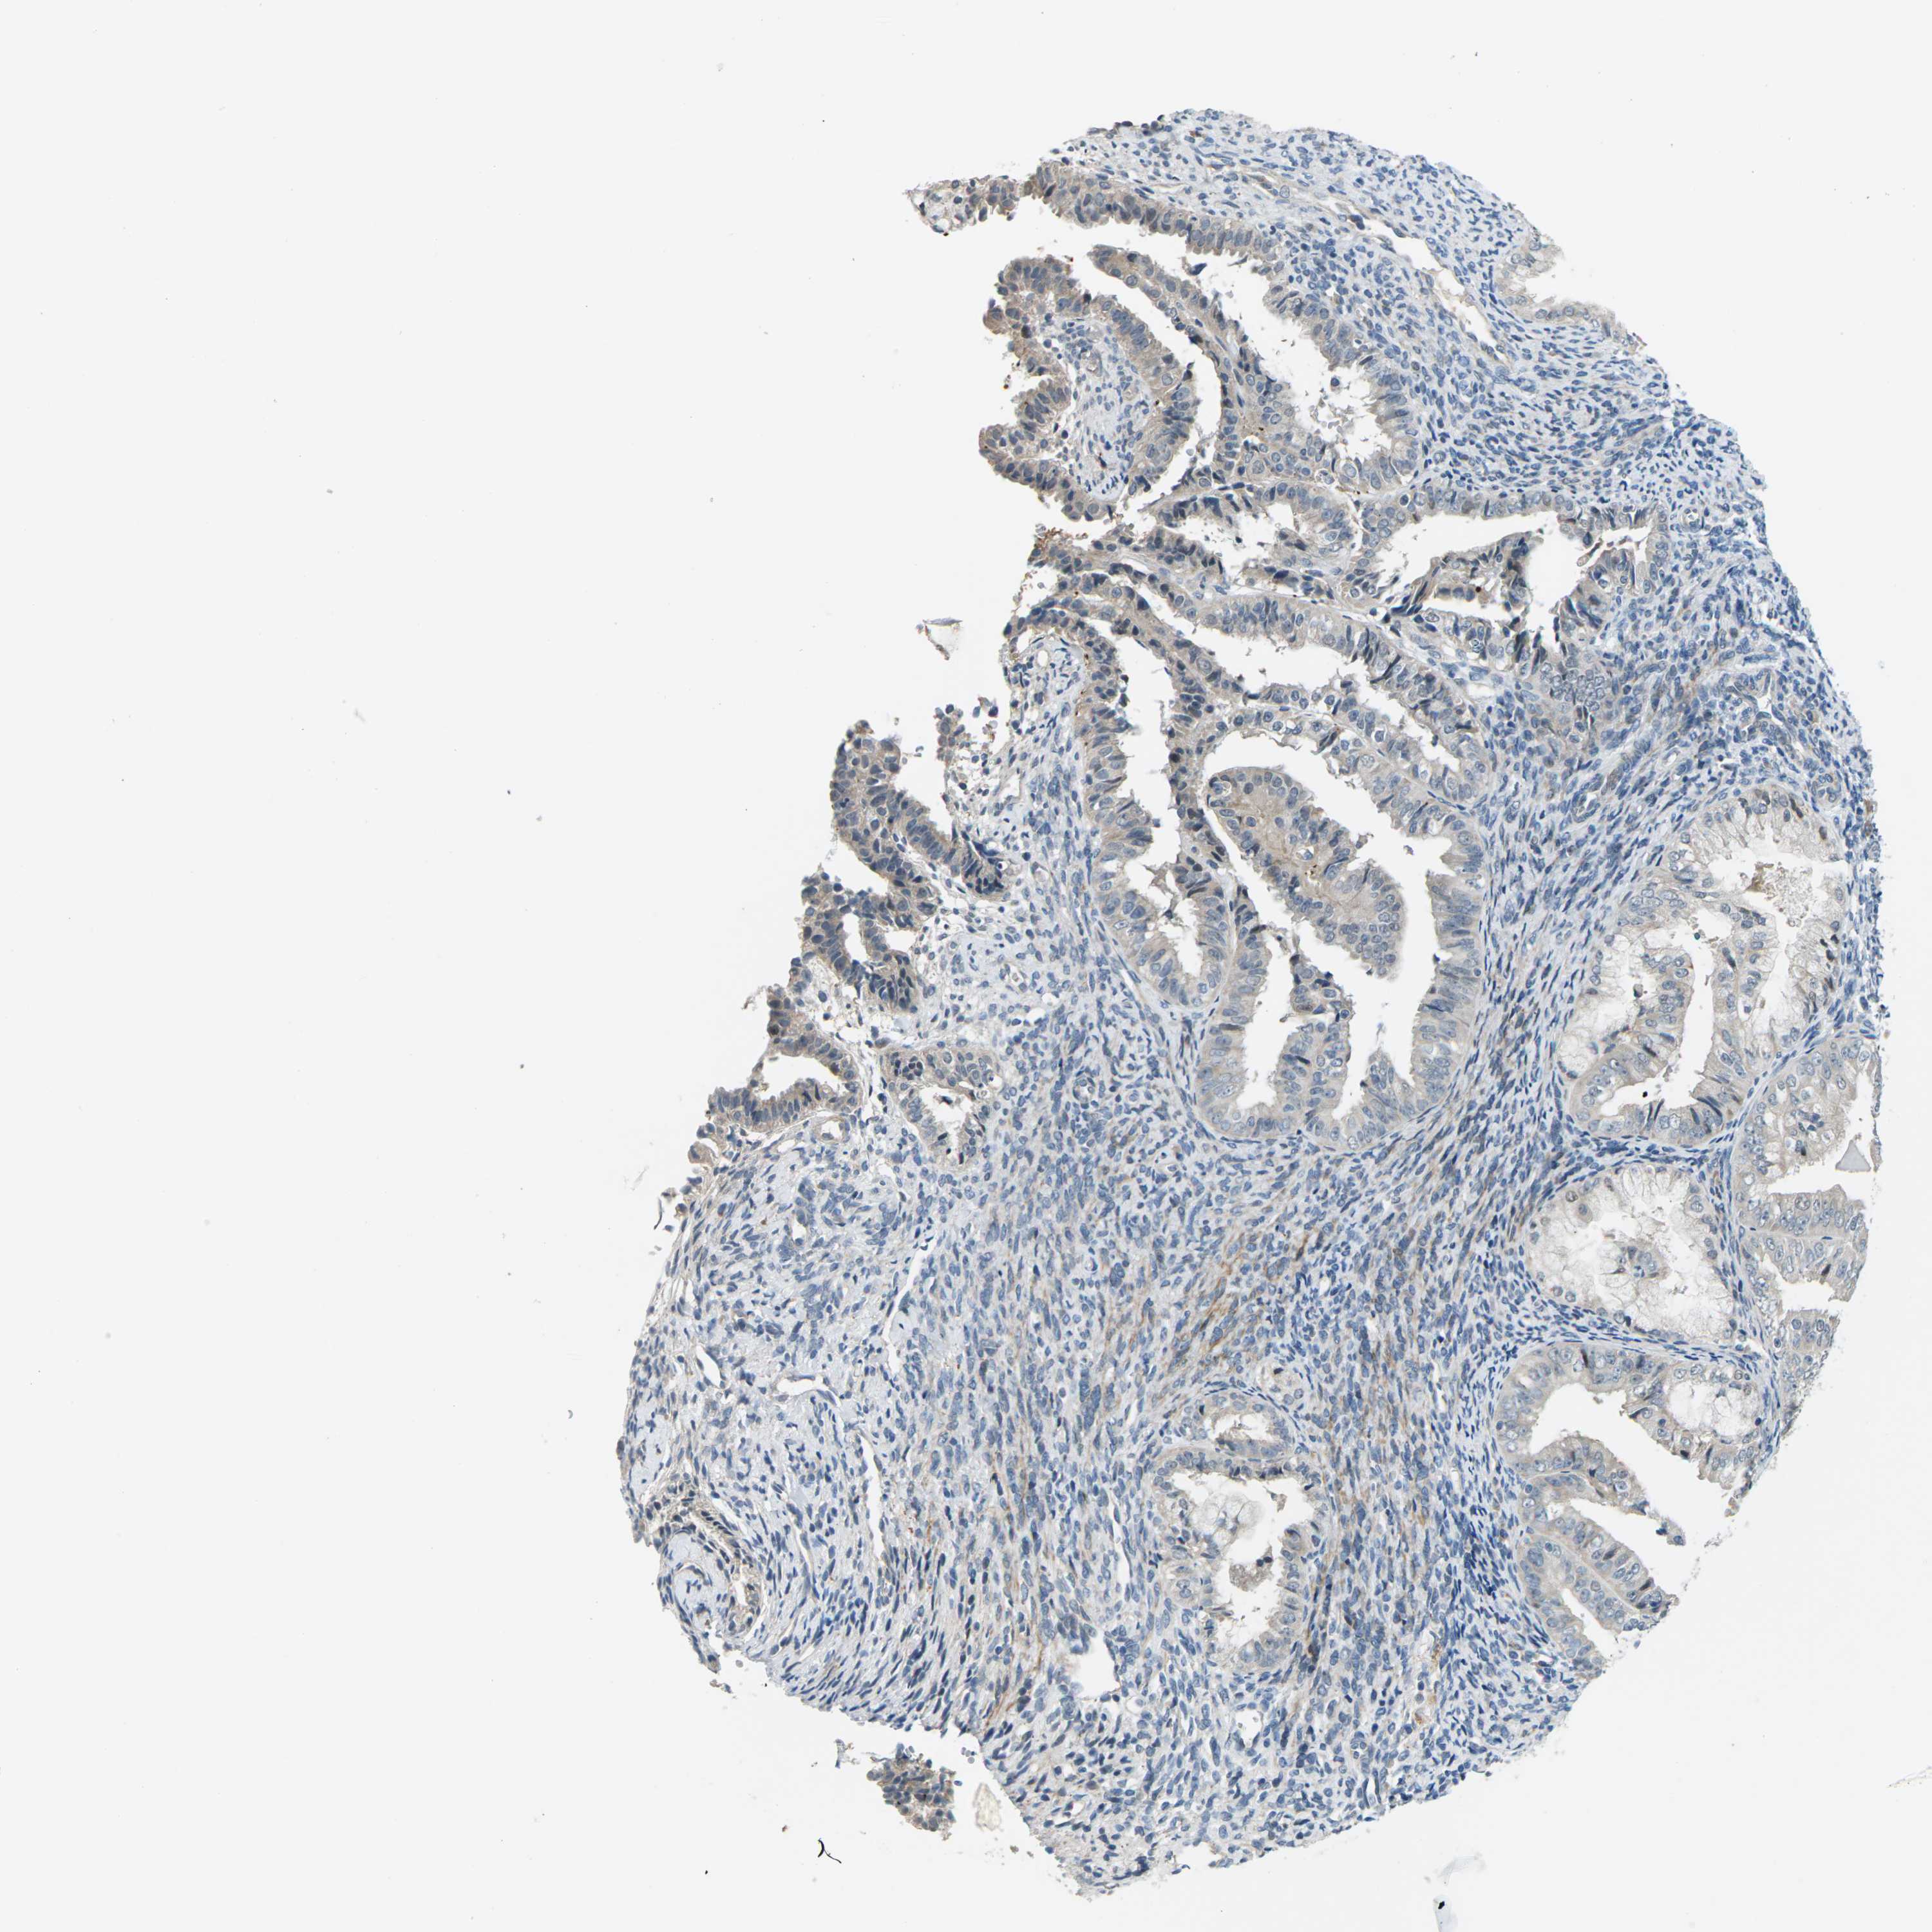

ENDOMETRIAL CANCER - Protein expressioni

A mouse-over function shows sample information and annotation data. Click on an image to view it in a full screen mode. Samples can be filtered based on level of antibody staining by selecting one or several of the following categories: high, medium, low and not detected. The assay and annotation is described here.

Note that samples used for immunohistochemistry by the Human Protein Atlas do not correspond to samples in the TCGA dataset.

Antibody stainingi

Antibody staining in the annotated cell types in the current human tissue is reported as not detected, low, medium, or high, based on conventional immunohistochemistry profiling in selected tissues. This score is based on the combination of the staining intensity and fraction of stained cells.

Each image is clickable and will lead to virtual microscopy that enables deeper exploration of all samples and also displays staining intensity scores, fraction scores and subcellular localization as well as patient and tissue information for each sample.

Antibody HPA014353

Antibody HPA014736

Staining

High

Medium

Low

Not detected

Intensity

Strong

Moderate

Weak

Negative

Quantity

>75%

75%-25%

<25%

None

Location

Nuclear

Cytoplasmic/membranous

Cytoplasmic/membranous,nuclear

Adenocarcinoma, NOS